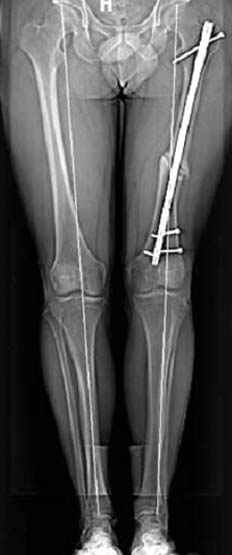

Выставлена на обсуждение (только одна проекция) рентгенограмма больного 25 лет, поступившего в приемное отделение, молодой дежурный врач сомневается в тактике лечения и спрашивает совета.

С его слов, больной стабилен,травму получил в результате автоаварии.Подскажите, что делать?Джолдас Кульджанов

5:24 Рентгенограмма таза, вызывают врача ортопеда (снимок N1), его диагноз: закрытый переломо-вывих правого тазабедренного сустава, получает добро на закрытую репозицию в приемном отделении

5:38 Дважды неудачная попытка закрытой репозиции в приемном отделении

6:20 ответстенный врач принимает решение о репозиции в условиях операционной, предупреждаются родственники и больной, что при неудачной закрытой репозиции, о возможности открытой репозиции и фиксации задней стенки вертлужной впадины.

7:30 начало операции, больной на спине, попытка репозиции после анестезии N3, укладка больного на боку, доступ Kocher- Langenbeck, состояние седалищнего нерва около 2.5см кровоподтек, через joistick головка бедра приподнята, освобовождение сустава, фрагмент заднего края более 3х4 см репонирован на свое место. После промывания

сустава, репозиция вывиха (N4), фиксация фрагмента 2.7(4) мм шурупами и допольнительно реконструктивной пластиной на 8 дырок, фиксация 3.5мм шурупами проксимально и дистально.

Интраоперционные N5 косая запирательная и N6 подвздошный снимок

11:50 больной в послеоперационной, рентгенограмма N7, компьютерная томограмма в тот же день N8-10